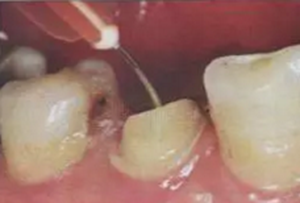

(冠部及根管全酸蝕)

(三用槍沖洗)

(注射器沖洗)

(根管毛刷清洗)

臨床建議用注射器、三用槍和柱狀毛刷,三者聯(lián)合反復(fù)沖洗。如再配合超聲波振蕩沖洗更佳。